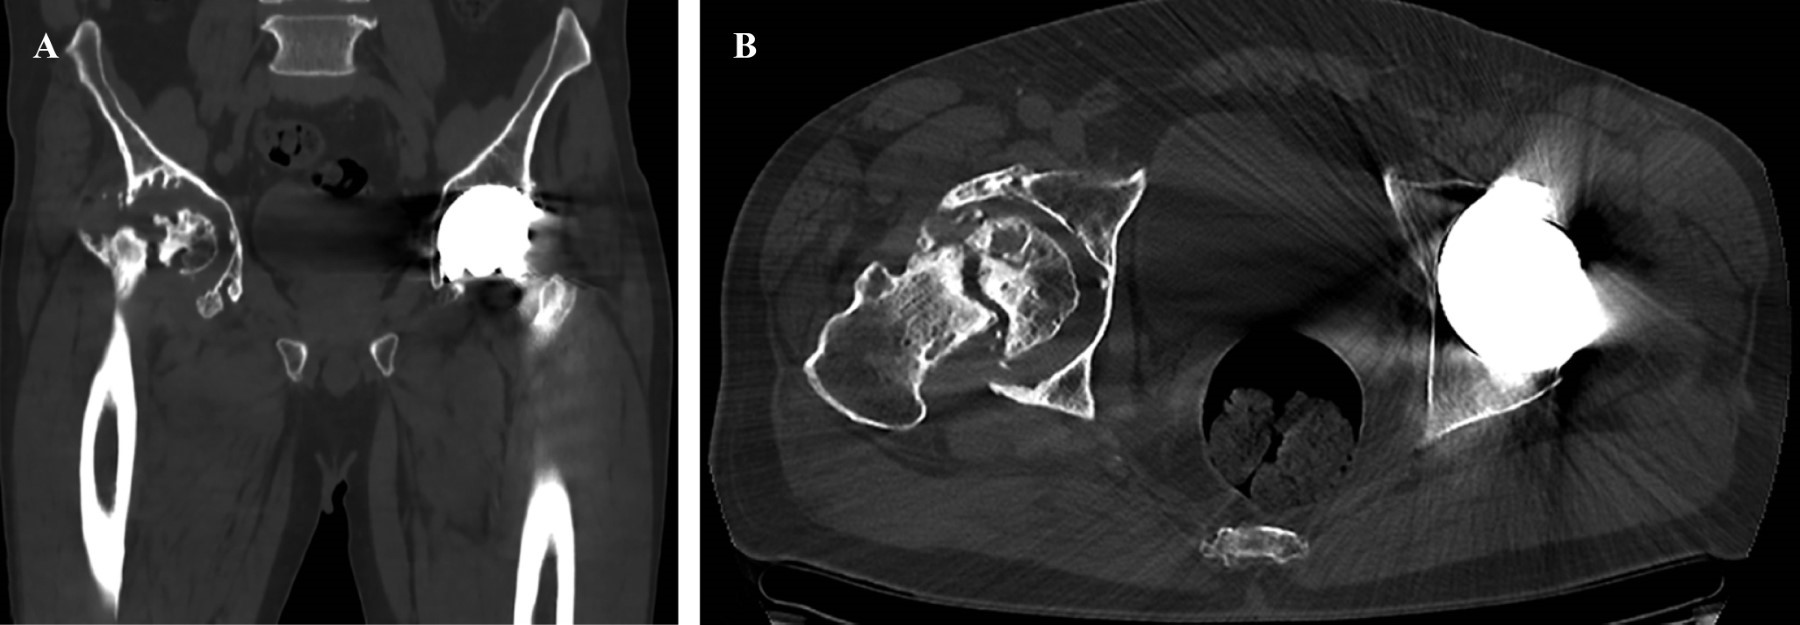

Se realiza radiografía anteroposterior (AP) de pelvis donde se observa pérdida de la esfericidad de la cabeza femoral, presencia de osteofitos, esclerosis con colapso subcondral, disminución del espacio articular, todo compatible con cambios degenerativos avanzados que se acompañan de cambios acetabulares secundarios a la osteonecrosis. En la cadera izquierda se observan componentes protésicos acetabular y femoral adecuadamente colocados y orientados, sin datos de interfaz, lisis o aflojamiento (Figura 1). Para identificar adecuadamente la morfología femoral y acetabular, se toma tomografía computarizada donde se aprecian múltiples quistes subcondrales, así como defecto óseo contenido, con pérdida considerable de hueso esponjoso principalmente de la pared posterior (Figura 2).

Dentro del abordaje diagnóstico se toman radiografías anteroposteriores de pelvis y tomografía computarizada para definir las características precisas del defecto acetabular. En este caso no se solicita resonancia magnética, debido a que este estudio se reserva para casos en etapas tempranas, en los que existe la sospecha clínica mediante interrogatorio y exploración física con radiografías normales.13

Figura 2